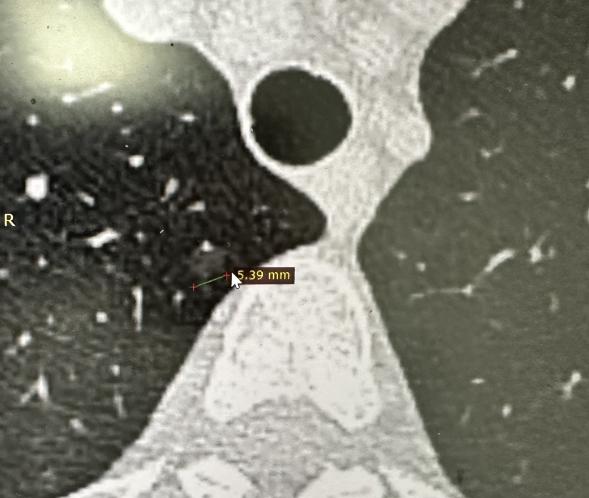

检查报告上出现 “磨玻璃结节” 这几个字,很多人第一反应就是担忧。但其实,并不是所有磨玻璃结节都需要立即手术,它有一套完整、科学的管理方案。 首先,我们得搞清楚什么是磨玻璃结节。它就是胸部 CT 扫描里,呈现出的一种低密度、半透明的模糊阴影。 根据数据统计,大概 20%~30% 的磨玻璃结节可能和肿瘤相关,多是最早期的病变或癌前病变。 但关键是,绝大多数这类结节生长非常缓慢,甚至长期不生长,只需要定期观察。 针对不同情况,我们有明确的管理策略: 1、该观察的:对于肺磨玻璃结节,经过随访没有变化,医生会根据形态特征、密度等,建议您6个月或1年复查一次,看它有没有变化。 我一般是推荐第一次3个月复查,两年内半年复查一次,超过两年就一年复查一次,不变化就一直复查。 2、该出手的: 如果结节在随访中出现增大、密度变高、出现实性成分等新特征,说明它在生长,就需要及时干预了。 3、该选消融的: 对于高龄、心肺功能差无法手术,或结节位置特殊、切除肺组织太多不划算的情况,介入消融是很好的选择。 无论是射频、微波还是冷冻消融,都能通过 CT 或导航支气管镜精准定位,直接 “灭活” 结节。 4、该放疗的: 对于 1~2 公分,又持续长大的结节,尤其是高龄、无法手术的患者,立体定向放疗效果确切,创伤小、恢复快。 最后,医生会结合结节的大小、密度、形态,以及你的家族史、吸烟史等个人情况,为你制定个性化的方案。 生活中,养护肺部同样重要。戒烟、远离二手烟是基础;同时减少粉尘、辐射等职业暴露。保持均衡饮食、适度锻炼和充足睡眠,才能真正筑牢肺部健康的防线。 发现磨玻璃结节不必恐慌,但也绝不能掉以轻心。最重要的一步,是和专业医生充分沟通,共同制定最合适的随访与治疗计划。[作揖][玫瑰]